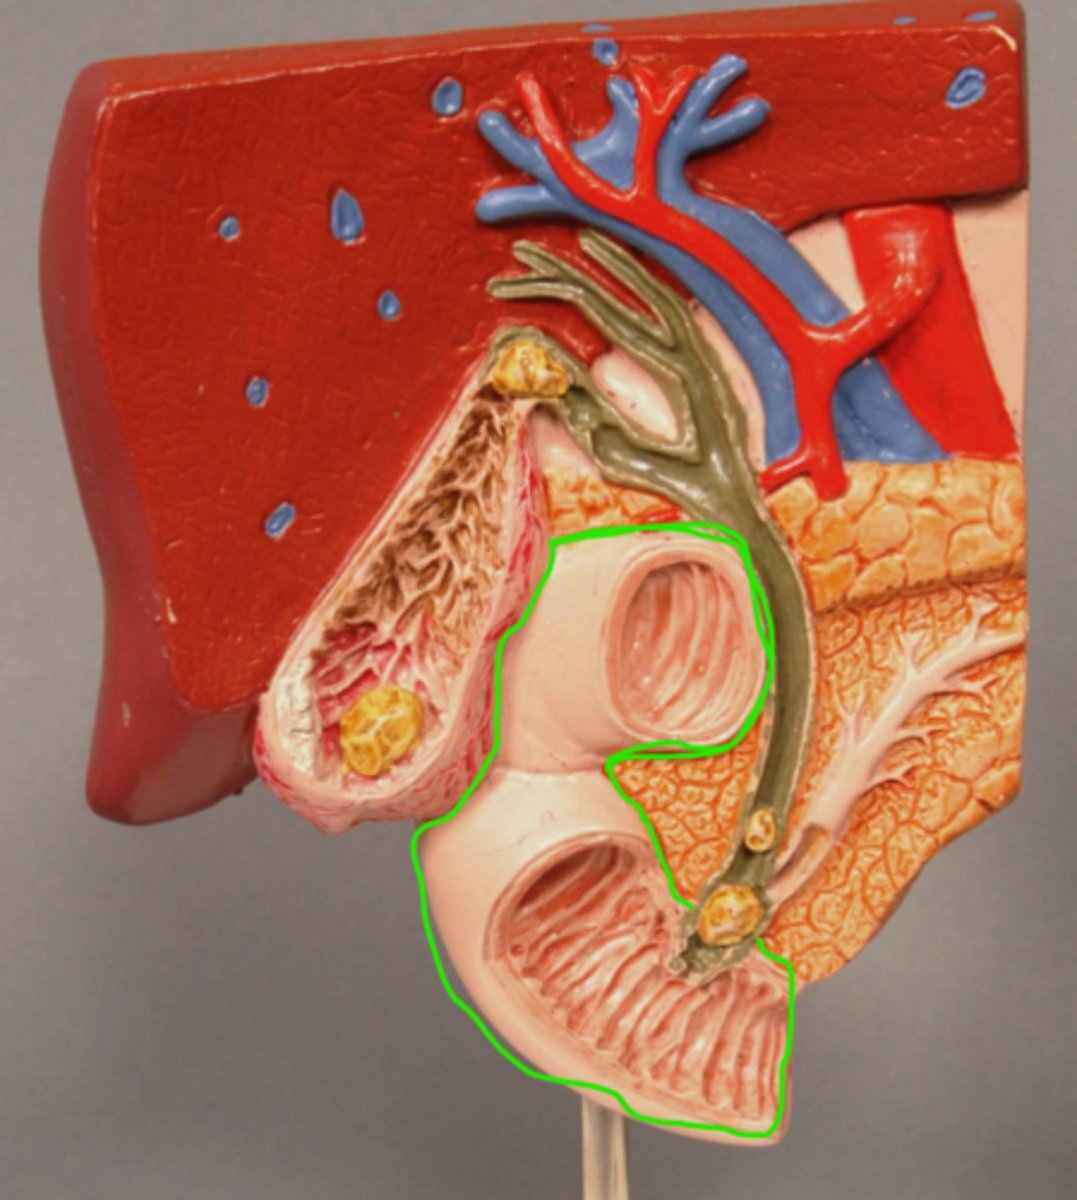

Duodenum

Sphincter of Oddi

Gallstone in Bile Duct

Gallstone in Ampulla of Vater